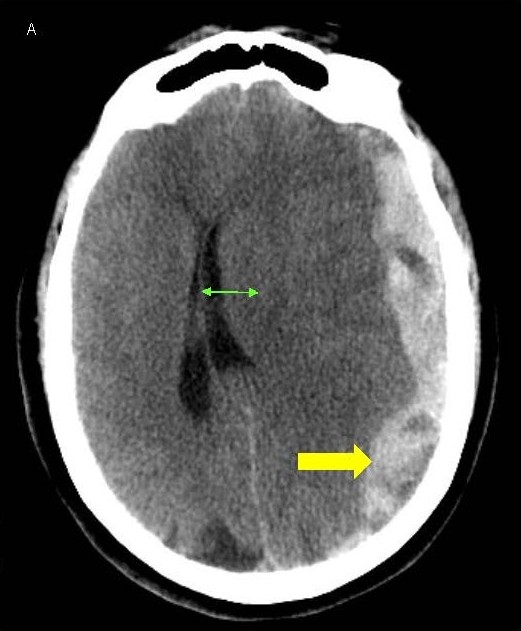

A 64-year-old woman presented to our emergency room with sudden onset severe headache and word finding difficulty that progressed to include lethargy and confusion. She had a history of pulmonary embolism treated with warfarin therapy, along with ischemic heart disease and heart failure, being treated with clopidogrel and controlled hypertension as well. She was disoriented to time and place and complained of a headache and word finding difficulty but had an otherwise normal exam. Lab tests were unremarkable other than an elevated PT-INR of 2.6 from warfarin. CT scans revealed a moderately large subdural hematoma over the left hemisphere, 2 cm thickness, with significant midline shift of 1.7 cm to the right and early left uncal herniation as well (Figures 1A and 1B). Due to the high risks of morbidity or mortality from the large hematoma and significant midline shift and herniation, aggressive treatment was instituted. She was given prothrombotic agents for reversal of warfarin and underwent emergent decompressive craniectomy.

Figure 1. A, B) CT scans of the head showing LEFT sided subdural hematoma (yellow arrow) with midline shift (green arrow).